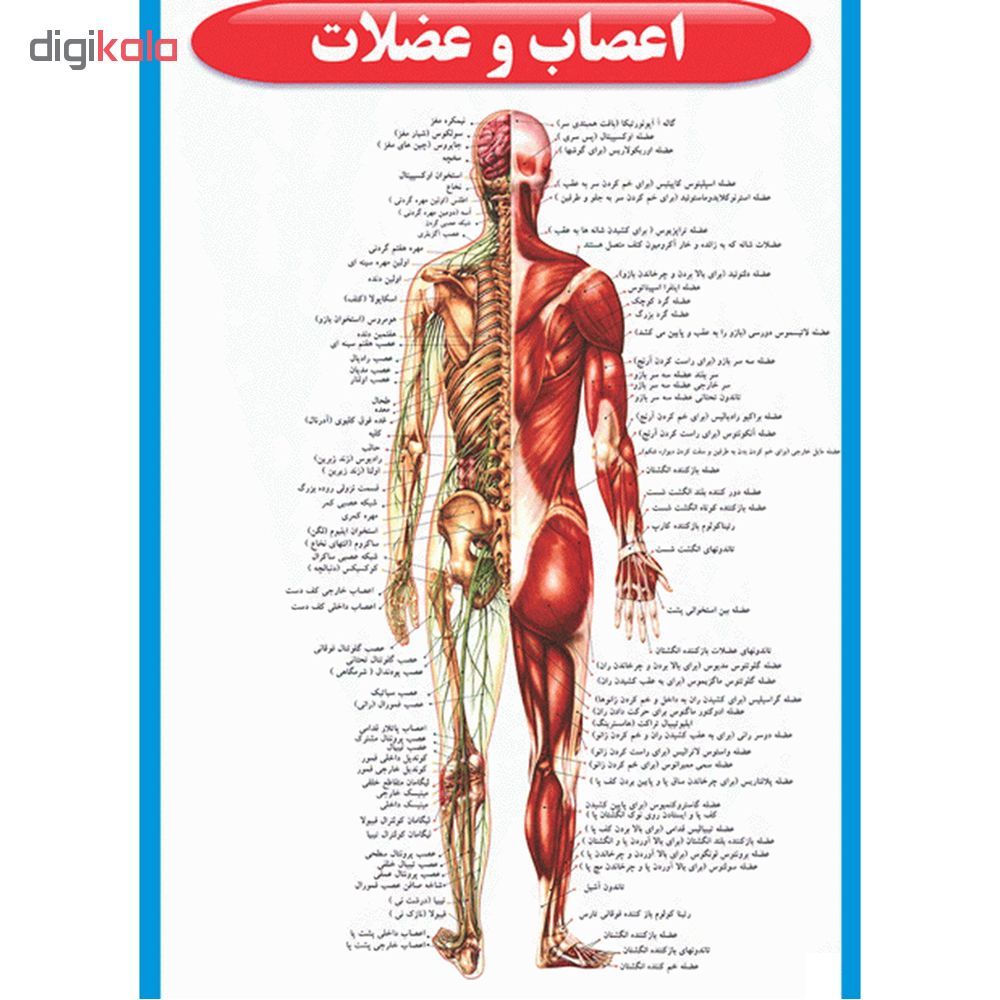

آناتومی سه بعدی بدن انسان عکس گرافی بدن.

اسکلت داربست بدن است تمام قسمت های بدن روی اسکلت قرارگرفته اند بدن انسان از ۲۰۶ قطعه استخوان تشکیل شده است این استخوان ها طوری با نظم کنار هم قرار گرفته اند که انسان را قادر می سازد حرکات دقیقی داشته باشد. استخوان یک نسج بسیار محکم است زیرا در ترکیب آن منرالها مانند کلسیم و دیگر وجود. اسکلت داربست بدن است تمام قسمت های بدن روی اسکلت قرارگرفته اند بدن انسان از ۲۰۶ قطعه استخوان تشکیل شده است این استخوان ها طوری با نظم کنار هم قرار گرفته اند که انسان را قادر می سازد حرکات دقیقی داشته باشد. آناتومی سه بعدی بدن انسان عکس گرافی بدن امعاء و احشاء بدن آناتومی سه بعدی بدن انسان عکس گرافی بدن امعاء و احشاء بدن قلب کبد روده.